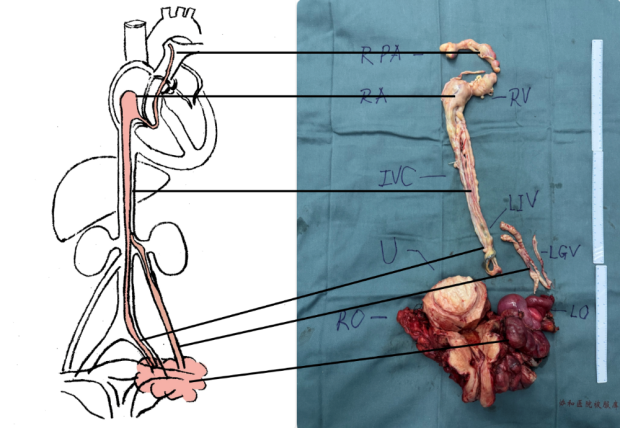

前述步驟完成後,團隊又重複了一遍經食道超聲探測,確認沒有殘留才關腹關胸,手術結束。一條形似“蚯蚓”,跨越腹腔胸腔、長約近50cm的瘤栓被“捉”出來了。

術後記錄顯示,馬女士的手術從早上9點開台,一直做到下午6點,過程一切順利。期間,體外循環歷時112分鐘,深低温停循環僅2分鐘。這能避免臟器長時間缺血、衰竭等。

圖源:受訪者